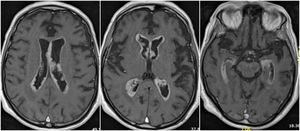

During neurological examination dysarthria, postural limb tremor with myoclonic interferences and cephalic myoclonus were found together with generalized increased tendon reflexes. The brain MRI images revealed an extensive pathological contrast uptake of the ependymal–subependymal surface, with variable and irregular thickness, throughout the infra- and supratentorial ventricular system (Fig. 1). No pachy- or leptomeningeal uptake of other brain parenchymal structures were observed. Blood analysis and toracoabdominal-pelvic CT scan were unremarkable. CFS examination revealed a lymphocytic predominant (83%) white blood cell count of 18/μL, a protein and ADA concentration of 266 mg/dL and 12,20 U/L; glucose, ACE and flow cytometry were normal. The microbiological research was negative, including tests for tuberculosis (mycobacterial culture, M.tuberculosis DNA and auramine stain), Toxoplasma gondii, Treponema pallidum, cryptococcus and virus (enterovirus, HSV-1, HSV-2, VZV and polyomavirus JC). CSF cytologic evaluation revealed an increased cellularity consisting mainly of lymphocytes and monocytes, and the presence of isolated epitheloid cells without striking atypical changes or mitosis. IHC study was inconclusive due to scarce material. The administration of pyracetam was effective for myoclonus and another lumbar puncture was planned to complete the IHC study.